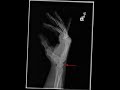

Triquetral fracture

This is a patient who presented with chronic wrist pain and clicking. Frontal and lateral radiographs of the wrist were obtained. The frontal radiograph demonstrates no radiographic abnormality. On the lateral radiograph as indicated by the red arrow, there is a well corticated osseous fragment on the dorsal aspect of the carpus. The corticated appearance as well as the absence of overlying soft tissue swelling is consistent with a chronic ununited fracture. A fracture in this location is consistent with a triquetral fracture. The triquetrum is the second most commonly fractured carpal bone. The most common carpal fracture is a scaphoid fracture. These types of fractures are extremely difficult to diagnose on the frontal radiograph. The location of the fracture fragment is typical for a triquetral fracture.